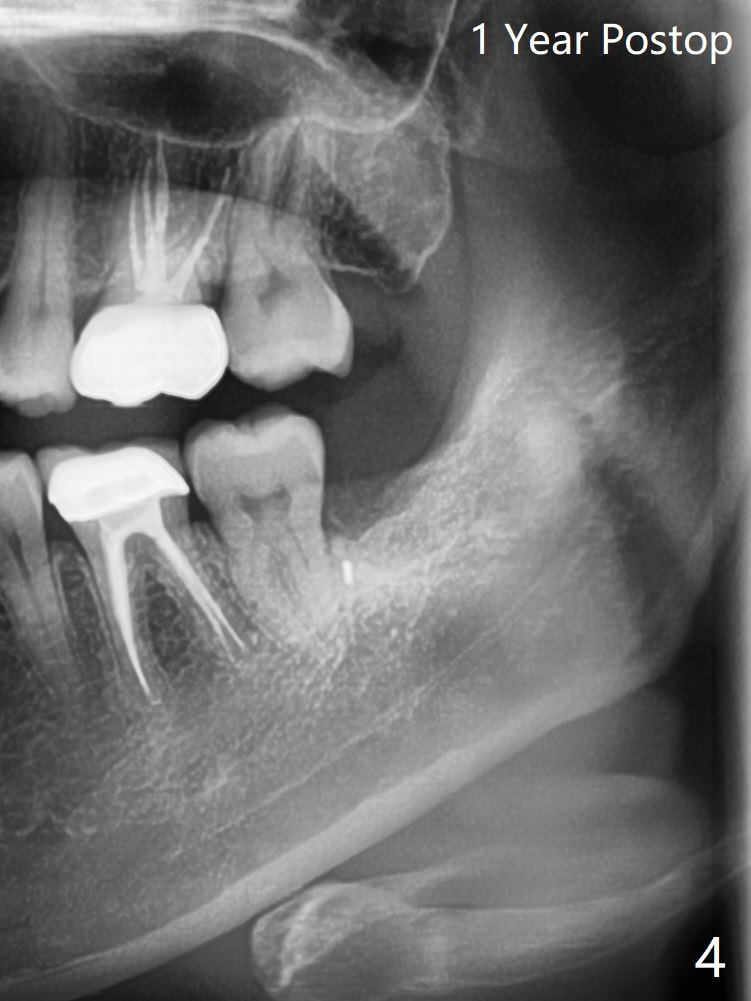

A 41-year-old woman (dental phobic) requests extraction of the tooth #17 because of food impaction (Fig.1). The fractured root tip (Fig.2 *) is so deep that the longest surgical length fissure bur can not reach in spite of multiple sectioning. The nervous patient agrees not to remove the root tip because of pain associated with root tip loosening. The fractured bur tip cannot be found clinically. CBCT should have taken for bur location and the proximity of the root tip to the Inferior Alveolar Canal. To prevent dry socket, Osteogen Plug is placed in the radicular portion of the socket (Fig.3 O), while allograft (A) in the coronal part of the socket. With Collagen Plug placed superficial to the allograft, 4-0 plain gut suture is used to close the socket. The patient returns 11 days postop with chief complaint of "pain returns for 2 days, affecting sleep. Small particles came out". #17 gingiva is healthy, although there is tenderness on deep palpation of #17 D. There is no exudate. Chlorhexidine irrigation is done with 2 syringes with pain relief. Augmentin is prescribed for 7 days. Pain disappears in ~ 1 month. Bone fills the socket 1 year postop (Fig.4).